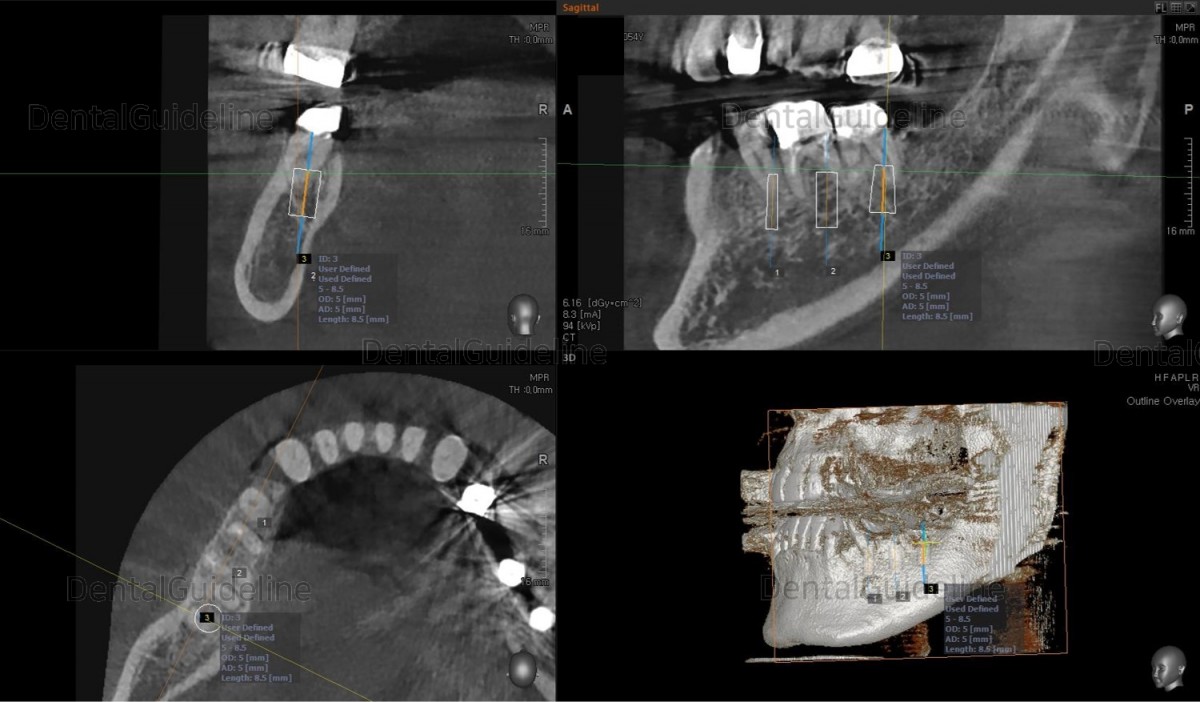

Surgery simulation to find the optimal

size, position, and direction of implants.

2nd premolar –Arum NB

Ø4.0L10 (30Ncm), 1st molar-Arum NB

Ø5.0L10 (40Ncm), 2nd molar-Arum NB

Ø5.0L10 (30Ncm),